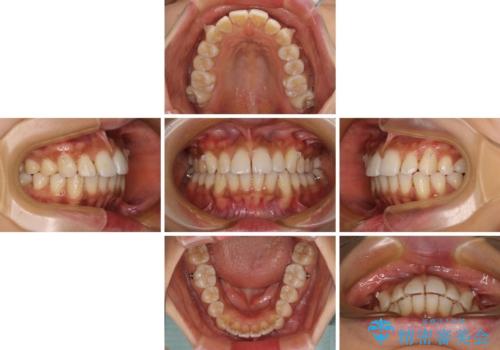

- 全体的な歯列の叢生を気にして来院された患者様です。

奥歯の咬み合わせを見ると、片方は上顎が下顎に対して相対的に前方にある状態でした。

咬み合わせを改善するためには、上顎臼歯を後方に移動させた咬み合わせにする必要があります。

インビザライン単体で改善することも可能ですが、ディープバイトのためインビザライン単体で達成する可能性が低いと考えられたため、カリエール・ディスタライザーという補助装置を併用して、より確実性を上げることとしました。

奥歯の咬み合わせ改善後に、インビザラインにて歯列を整えることとしました。